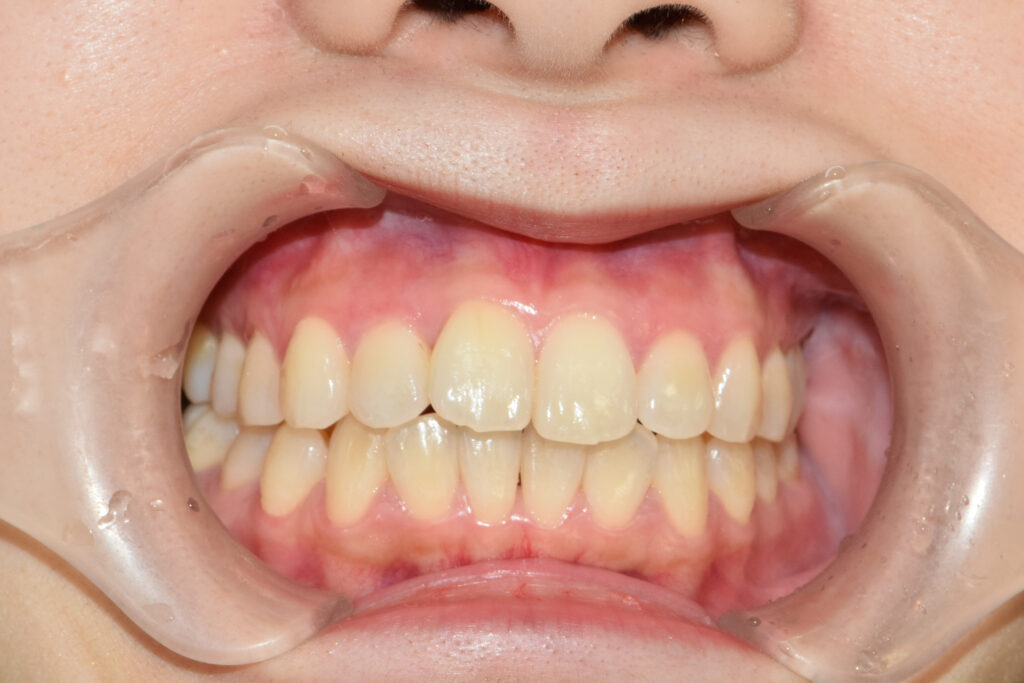

正面

治療前